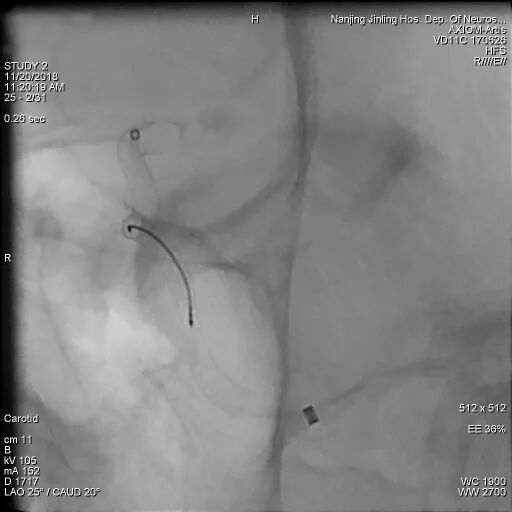

Pipeline Flex在送至瘤颈口处时,因瘤腔巨大,支撑力不足,微导管多次疝入瘤腔内,术者随即尝试将Navien上高通过瘤颈,但多次尝试后因远端血管扭曲而失败。

随后术者决定使用球囊锚定微导管技术,从左侧股动脉穿刺置管上球囊,经右侧颈内动脉A1段,通过前交通动脉到达左侧大脑中动脉M1段,同时新的Marksman也超选到左侧大脑中动脉M2段。

充盈球囊后锚定Marksman微导管,顺利将Pipeline Flex输送通过瘤颈至左侧大脑中动脉M1段。